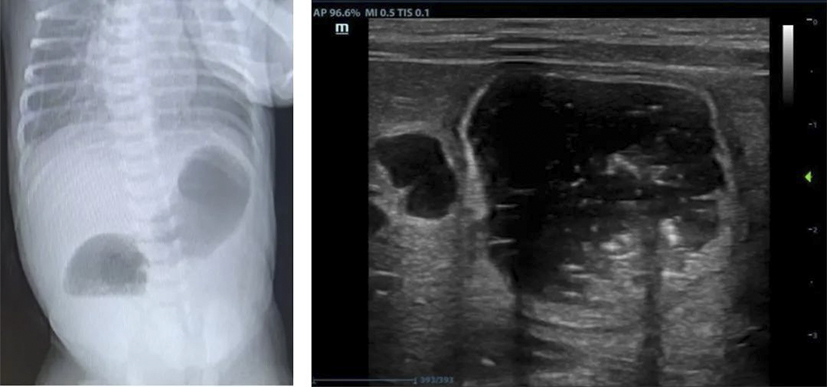

十二指腸閉鎖是一種先天性消化道畸形,發(fā)病率約1/50000至1/10000,占所有腸閉鎖的50%以上,約30%合并唐氏綜合征,也可能伴隨其他先天異常(如心臟畸形、腸旋轉(zhuǎn)不良等)。產(chǎn)前主要表現(xiàn)為母體羊水過多,超聲可見胃和十二指腸近端擴張(“雙泡征”)。出生后表現(xiàn)為24-48小時內(nèi)嘔吐、上腹部膨隆、排便減少或無胎糞排出等。通過產(chǎn)前超聲、出生后X線檢查可以明確診斷,手術是唯一的治療方法。微創(chuàng)腹腔鏡手術具有創(chuàng)傷小、出血少、術后恢復快、縮短住院時間等優(yōu)勢,目前已廣泛應用于十二指腸閉鎖的治療。